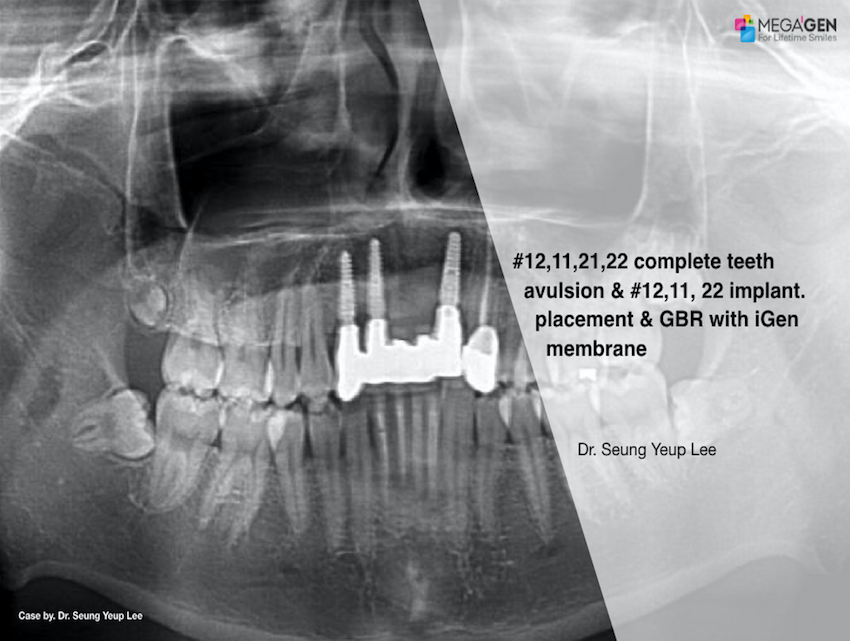

Keywords

e.g. product name, treatment solution, author, clinician name